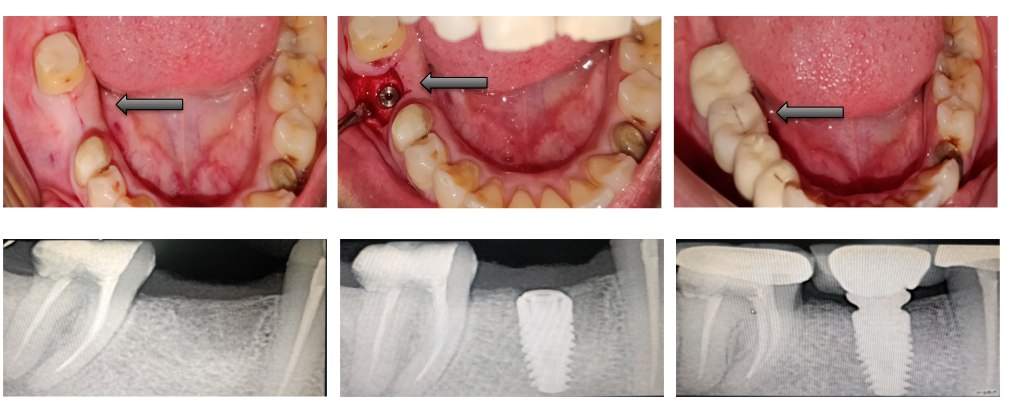

Single Tooth Replacement

Multiple Teeth Replacement